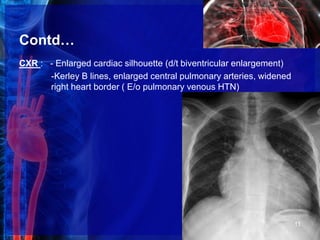

CXR : - Enlarged cardiac silhouette (d/t biventricular enlargement)

-Kerley B lines, enlarged central pulmonary arteries, widened

right heart border ( E/o pulmonary venous HTN)